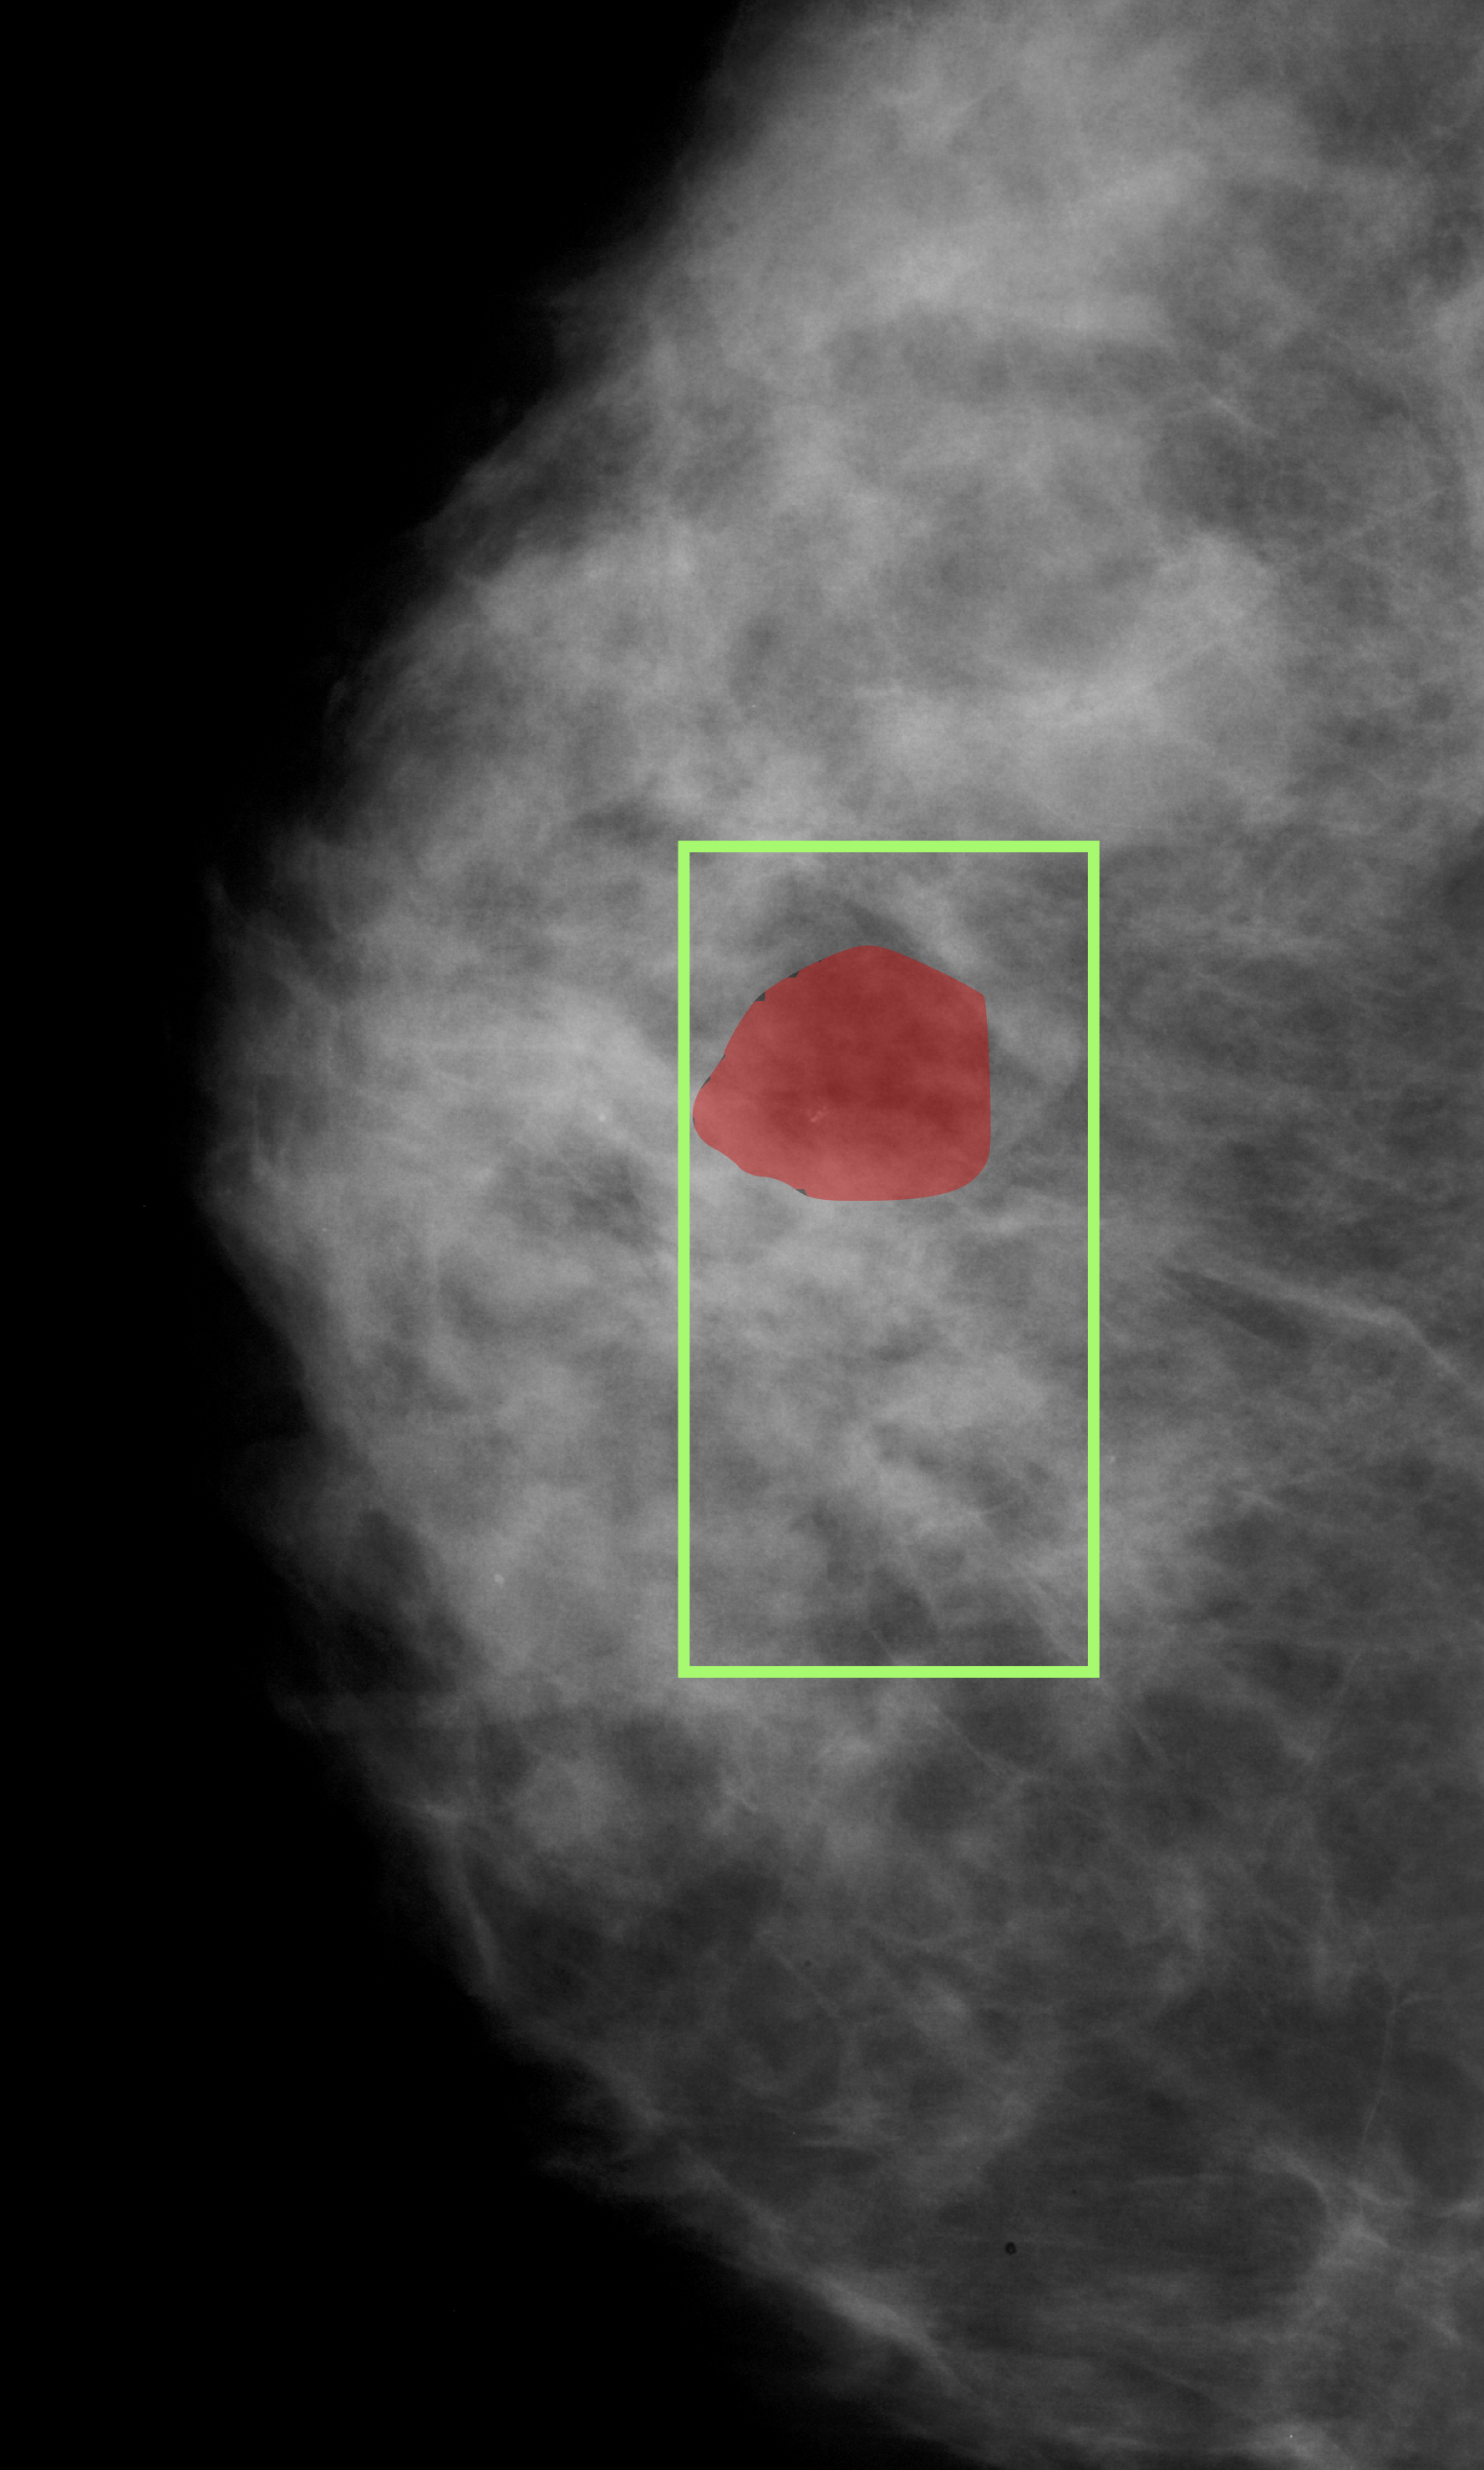

Figure 5: Breast cancer detection. Green - Predicted ROI, Red - Ground Truth.

The proposed approach was also applied to breast cancer detection (for screening) from mammograms. Unlike the DME problem, evidence for breast cancer is not easily discernible to the naked, untrained eye and hence is particularly challenging. The 2 classes of interest were defined to be normal and abnormal. The latter includes benign and malignant cases as discrimination between these cases is difficult and best done by a specialised model. The ROI prediction aimed at are suspect regions regardless of whether they are benign or malignant. The architecture used for the DME problem was used and patches from the entire mammogram was fed as input. Training methodology was as described in section 2.3. The patches(200x200) which were classified as positive by the model acts as the predicted ROI in the large sized mammogram image(around 4000x4000 in dimension). The model was assessed on CBIS-DDSM dataset [14]. A total of 5218 training images (2017 abnormal and 3201 Normal) were split into train and validation in the ratio of 12:5. A model trained on 1:3 ratio of annotated images, was evaluated on a test set of 1298 images(709 abnormal and 589 Normal). The AUC/sensitivity(SN)%/specificity(SP)% attained was 0.98/90/93 respectively. Three sample images with ground truth regions and model-predicted ROIs(bounding boxes) are shown in Fig.5. A baseline model(Mbsubscript𝑀𝑏M_{b}) was also trained and tested. It achieved a AUC/SN/SP of 0.972/88.2/ 91.3 respectively. A recent method [15] that does normal/cancerous classification also reports on [14]. It is based on transfer learning with a Resnet50 and reports AUC/SN/SP to be 0.91/86%/80.1%.